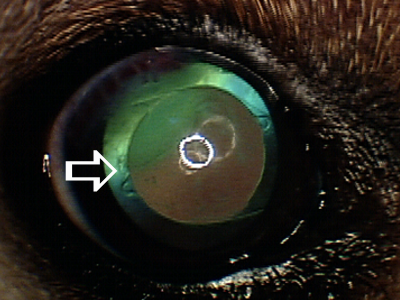

Cataract surgery is effective method for permanently removing cataracts and restoring normal vision. Artificial lens (white arrow) is usually placed in the eye with a goal of correcting vision to the normal levels. Removal of cataracts eliminates risks of chronic cataract-induced inflammation, and associated complications, which may result in blindness and loss of eye (retinal detachment, glaucoma, intraocular hemorrhage).

Cataract surgery is effective method for permanently removing cataracts and restoring normal vision. Artificial lens (white arrow) is usually placed in the eye with a goal of correcting vision to the normal levels. Removal of cataracts eliminates risks of chronic cataract-induced inflammation, and associated complications, which may result in blindness and loss of eye (retinal detachment, glaucoma, intraocular hemorrhage).